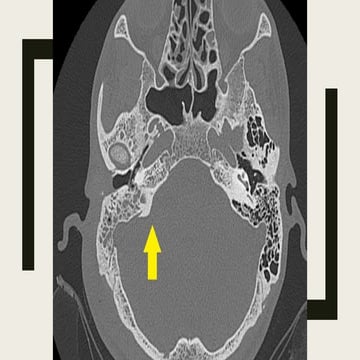

Mucor fungus ball in a 49-year-old woman with chronic sinus pressure

and halitosis, unenhanced CT scan shows isoattenuating to

hyperattenuating material filling the right maxillary sinus with central

calcific areas of increased attenuation (long arrow), note the

circumferential thickening of the osseous walls of the sinus (short

arrows), a finding consistent with a chronic inflammatory process